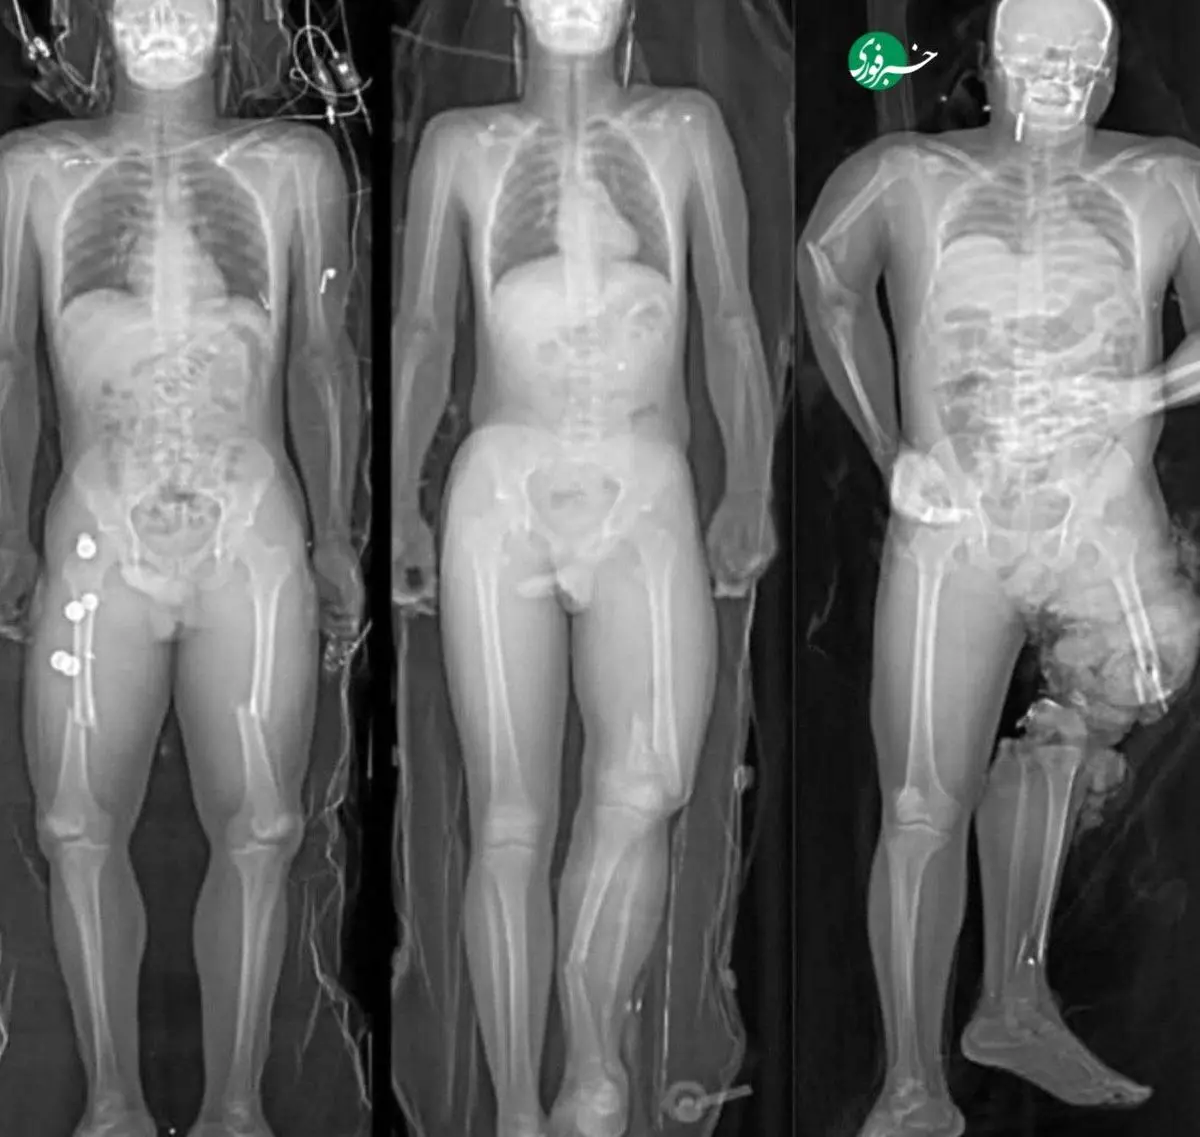

در یک تصادف جاده‌ای، سه سرنشین بدون کمربند ایمنی آسیب‌های شدیدی دیدند که تنها به دلیل نحوه نشستن‌شان متفاوت بود.

سمت چپ: پاها روی هم؛ بدن پیچ‌خورده و شکستگی‌های پیچیده در استخوان‌های پا.

وسط: نشستن عادی؛ آسیب کمتر، اما همچنان جدی.

سمت راست: پا روی داشبورد؛ کیسه هوا پا را به لگن کوبید و استخوان‌های لگن و ران خرد شد – آسیبی مادام‌العمر.